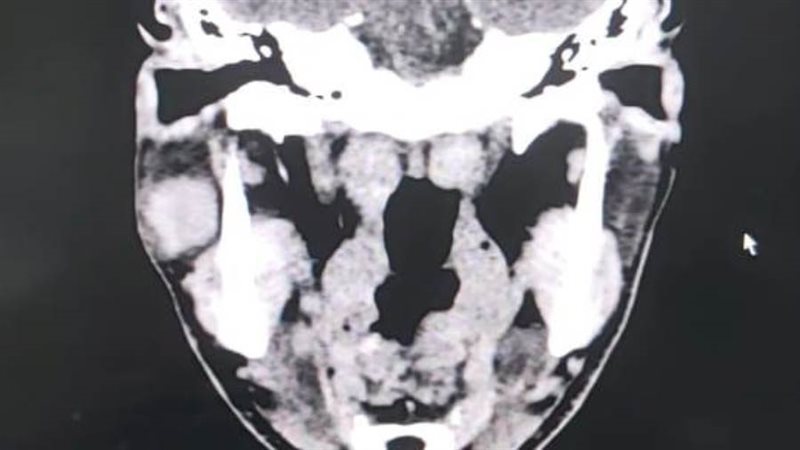

قام قسم جراحة الوجه والفكين بمستشفى ادكو المركزى فى إجراء عملية دقيقة لإزالة ورم من الغدة النكافية "ورم حميد بالغدة النكافيه من الفص السفلي لها" وبفضل الله تم الحفاظ على العصب الوجهي السابع.

قام بإجراء العملية نخبة من جراحي قسم جراحة الوجه والفكين بالمستشفى ، بقياده الدكتور وائل نمير استشاري جراحة الوجه و الفكين بالقسم، واشراف الدكتور أحمد بلال رئيس القسم ، والدكتور محمود قاسم ، والدكتور ضياء يس أخصائيين جراحة الفم والأسنان، والدكتور عبد الرحمن عيسى استشاري التخدير، وطاقم تمريض العمليات، وفنيي التخدير.